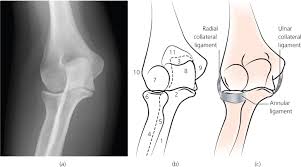

The common extensor tendon attaches to the lateral epicondyle, acting as the common attachment for the superficial extensor muscles of the forearm. The lateral epicondyle of the humerus is a large, tuberculated eminence, curved a little forward, and giving attachment to the radial collateral ligament of the elbow joint, and to a tendon common to the origin of the supinator and some of the extensor muscles. Tennis elbow assessment explore the. Related online courses on physioplus. Lateral epicondylitis is defined as a pathologic condition of the wrist extensor muscles at their origin on the lateral humeral epicondyle. This area can become tender to the touch. Pain is felt over the lateral epicondyle and radiates down forearm. Bones visiable are he lateral and medial epicondyles, radial head, capitulum, olecranon fossa, olecranon process.

An ununited fracture of the lateral condyle can lead to. The medial and lateral epicondyles are small bony tuberosities on the distal end of the humerus (fig. Lateral elbow is in contact with ir. Tennis elbow assessment online course: Resisted wrist extension with elbow fully extended.